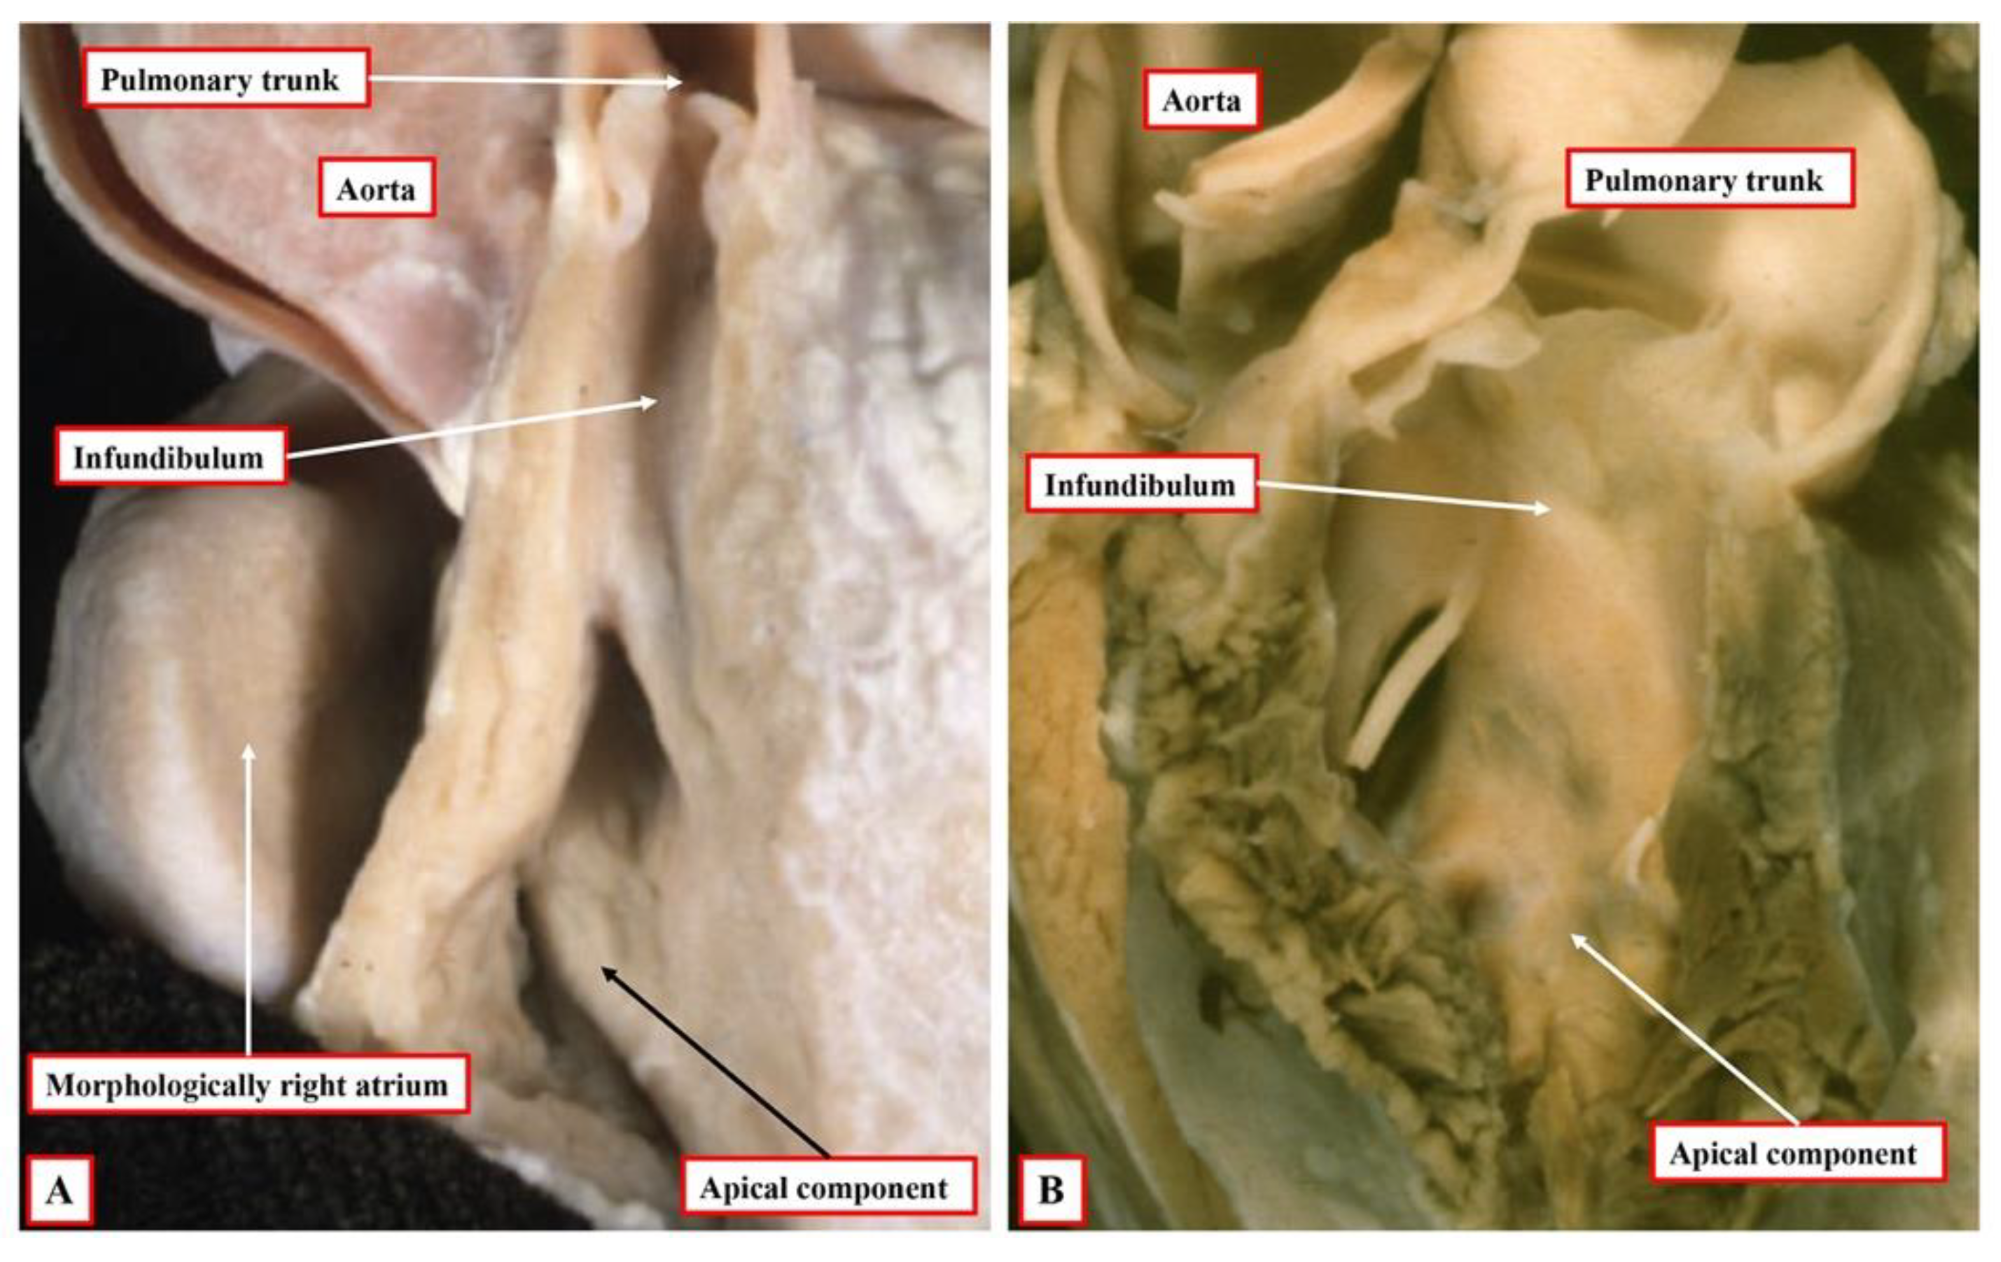

8. Is It Possible to Establish Ventricular Topology in Individuals with Univentricular Atrioventricular Connections and Dominant Left Ventricle?

As we have now demonstrated, the key to establishing ventricular topology is the ability to anchor the thumb in the inlet to the morphologically right ventricle. The essence of hearts having a univentricular atrioventricular connection to a dominant left ventricle is that the right ventricle is incomplete and rudimentary. This is because it lacks its inlet component. Indeed, when there is a double outlet from the dominant left ventricle, on occasion, it can lack both inlet and outlet components. Those using the segmental approach argue that, in the setting of hearts with univentricular atrioventricular connection to a dominant left ventricle, the second chamber present is no more than an infundibulum [

17]. There are multiple flaws in the logic underscoring this suggestion, not the least that, if the chamber were truly no more than an infundibulum, it would not be possible to diagnose transposition, which requires the aorta to arise from the morphologically right ventricle or its rudiment. As we have already shown, the evidence is now overwhelming from cardiac development that, from the outset, the small chamber in hearts with a dominant left ventricle possesses an apical trabecular component of right ventricular morphology (

Figure 2B).

At the initial stage, however, as also explained, the developing right ventricle lacks its inlet component. It is not possible, therefore, to establish its topology with certainty since it is not possible to anchor the thumb. This remains a problem when seeking to establish topology in postnatal hearts with univentricular atrioventricular connection to a dominant left ventricle, such as double inlet left ventricle or the commonest variant of tricuspid atresia. In most instances, nonetheless, it is possible to infer the likely ventricular topology according to the location of the incomplete ventricle. Almost without exception in these settings, the incomplete right ventricle is carried on the shoulder of the dominant left ventricle. When there is usual atrial arrangement, therefore, a right-sided and anterior location of the incomplete right ventricle can be taken as evidence of right-handed topology, for example, in the heart with tricuspid atresia, as shown in

Figure 1A.

The possibility to make such inferences can also be seen in hearts with a double inlet left ventricle and concordant ventriculo-arterial connections. This lesion is usually known as the “Holmes heart”, with the pulmonary trunk spiralling into the mediastinum having taken origin from an anterior and right-sided incomplete right ventricle (

Figure 8A). On occasion, however, the concordantly connected pulmonary trunk can take its origin parallel to an anterior aorta from a left-sided and anterior incomplete right ventricle (

Figure 8B).

The inference can be made that, in the “classical” Holmes heart, there is right-handed ventricular topology. In the heart shown in

Figure 8B, in contrast, the inference is that, had the tricuspid valve been formed properly, it would have entered the left-sided morphologically right ventricle. Hence, there is left-handed ventricular topology. This finding, however, does create problems for those using segmental notation. This is because the heart shown in

Figure 8B would correctly be listed as having a double inlet left ventricle {S,L,D}. This notation, however, could also be correct for hearts having the usual form of double inlet left ventricle with discordant ventriculo-arterial connections, but with a right-sided aorta arising from the left-sided incomplete right ventricle. For those using the segmental approach, therefore, it would also be necessary to arbitrate for the concordant ventriculo-arterial connections in the heart shown in

Figure 8B. Those using the sequential approach do not encounter this problem since the description of double inlet left ventricle with left-sided incomplete ventricle and concordant ventriculo-arterial connections is explicit.